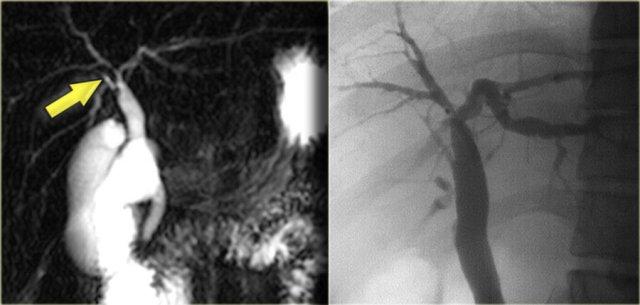

Bên trái là hình ảnh MRCP của một bệnh nhân mắc PSC.

Lưu ý chỗ hẹp lớn, rất đáng lo ngại cho ung thư đường mật (mũi tên).

Các chỗ hẹp trong PSC thường có sự chuyển tiếp đột ngột, trong khi ở đây chúng ta thấy hình ảnh “vai” (shouldering), gợi ý hiệu ứng khối.

Ngoài ra, có giãn đường mật trong gan ở phía thượng lưu vùng hẹp này.

Bên trái là hình ảnh MRCP của một bệnh nhân cho thấy chỗ hẹp ở mức rốn gan.

Trên MRCP, chỗ hẹp này trông dài và đáng lo ngại cho ung thư đường mật.

Tuy nhiên, trên ERCP, các ống mật đã được bơm căng bằng thuốc cản quang và chúng ta có thể thấy đây là một chỗ hẹp ngắn, phù hợp với chẩn đoán PSC.

Trong quá trình theo dõi, trường hợp này được xác nhận chỉ là PSC.